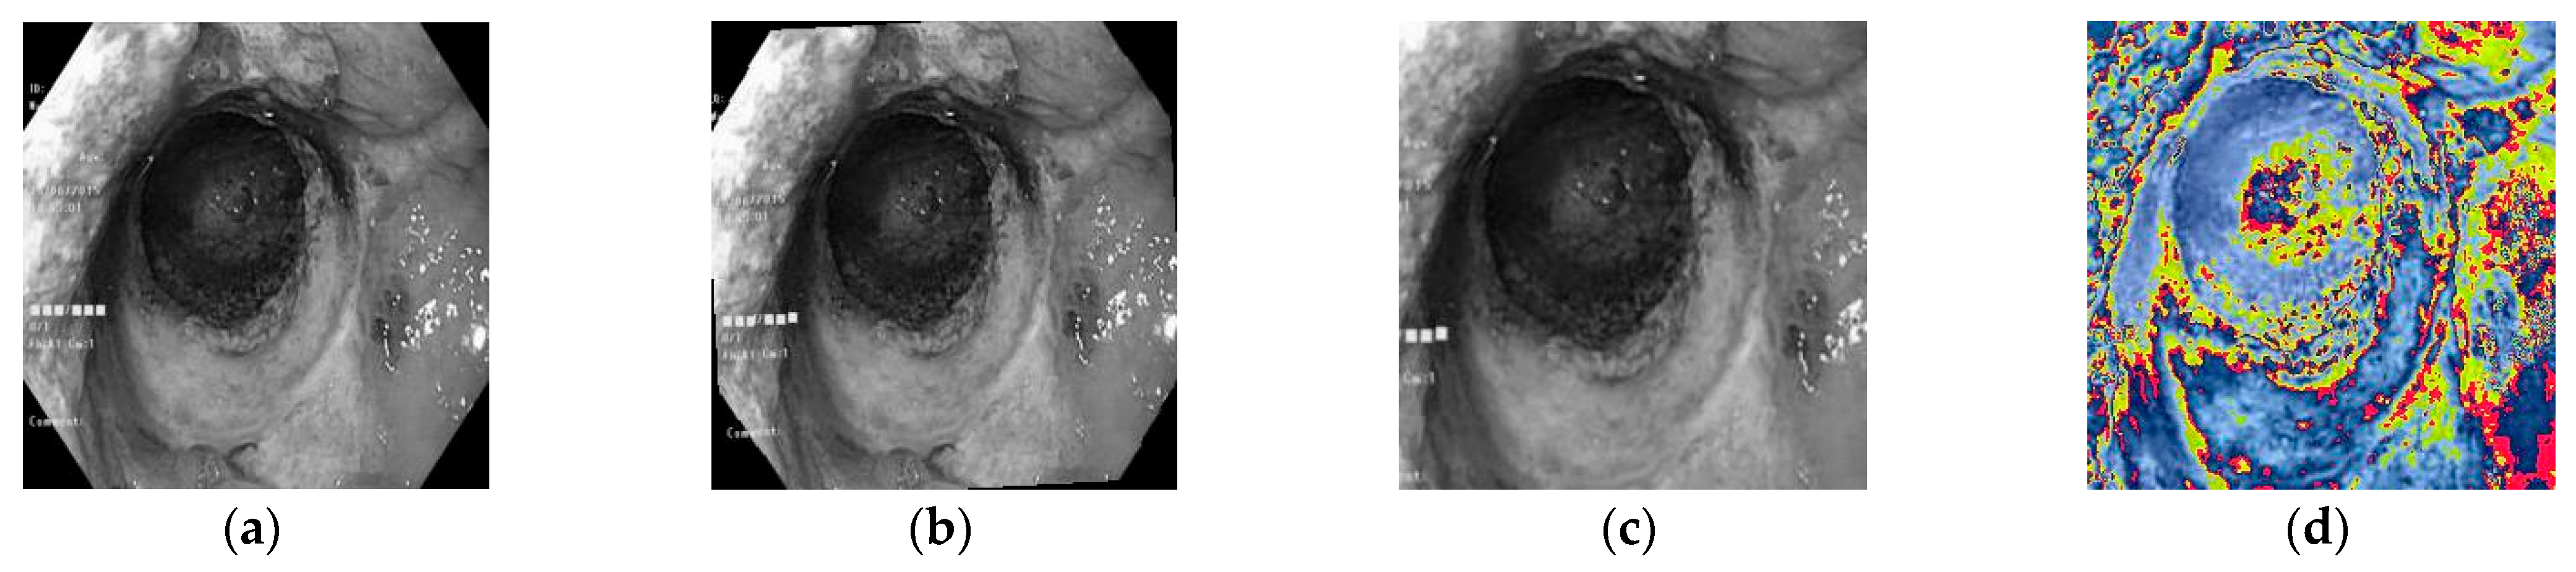

During the experiment, a center cropping operation is performed on the original picture. The images are randomly rotated 15 degrees, which helps to increase the diversity of the data and improve the generalization ability of the model. The image is enlarged to 1.25 times its original size, which is done to increase the diversity of the data while ensuring that the image is not distorted. The regularization process is carried out to standardize the pixel values of the image, so that it falls in a unified range, which is conducive to the training and convergence of the network. Taking an image in the fundus green-light dataset as an example, the image pre-processing process is shown in Figure 6.

Figure 6. Image pre-processing process. (a) Original drawing. (b) Randomly rotate 15°. (c) Cut and enlarge the center by 1.25 times. (d) Normalization.